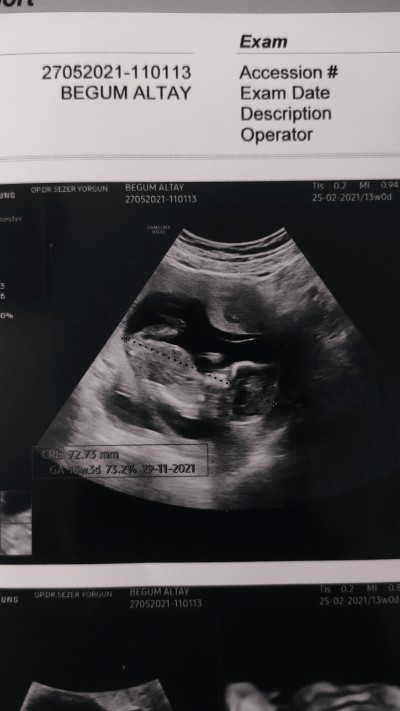

Merhaba arkadaşlar 13+3teyiz.nub teorisi falan cinsiyet tahmini yapabilen varsa bekliyorum . Allah'ım hepimize sağlıkla aldırsınn bebislerimizi kucağımıza

Gebelik haftası 14